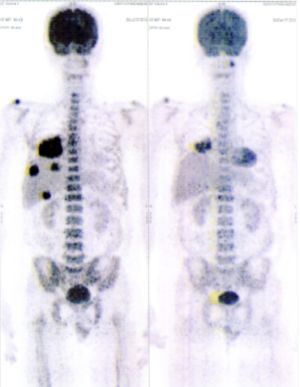

Below are some of the cases, from more than 80 cases we have treated so far with good results. When reading the PET/CT scans, the picture on the left is before treatment, and the picture on the right is after treatment. The intensity of black represents the activity of the cancer, but some black areas are not cancer: brain, heart, radioactive urine in bladder. For the heart, the intensity of black depends on the number of hours of fasting: if more than 10 hours, the heart is not even black, but if fasting is less than 6 hours, it is very black. The intensity of black in the brain can be variable in different scans depending on the brain activity at the time of the scan. The intensity of black in the radioactive urine can also be variable due to the hydration of patients and the time of injection of diuretic.

CASE NO: 1

(HEPATOCELLULAR CARCINOMA + STOMACH CANCER)

A middle-aged women who is very thin and very weak, can hardly walk, lying in bed most of the time. She saw a cancer specialist in a top hospital who discovered that she had massive hepatocellular carcinoma, and another cancer in the stomach. Given that hepatocellular carcinoma is incurable and stomach cancer is very difficult if not impossible to cure without surgery, she was told that nothing could be done for her. She came to ask us to help her. After just 4 treatment, the hepatocellular carcinoma went into remission, and the stomach cancer (arrow) became less active. Until today, more than 6 months later, the hepatocellular carcinoma is still in remission.

CASE NO: 1 - A FEW MONTHS LATER

A few months after successful treatment for hepatocellular carcinoma, and partially successful for stomach cancer, the PET/CT scan showed the stomach cancer becoming very active, with several metastases to the parts of the liver not previously involved by hepatocellular carcinoma. After a few treatment, all the active stomach cancer lesions in the stomach and in the liver went into remission.